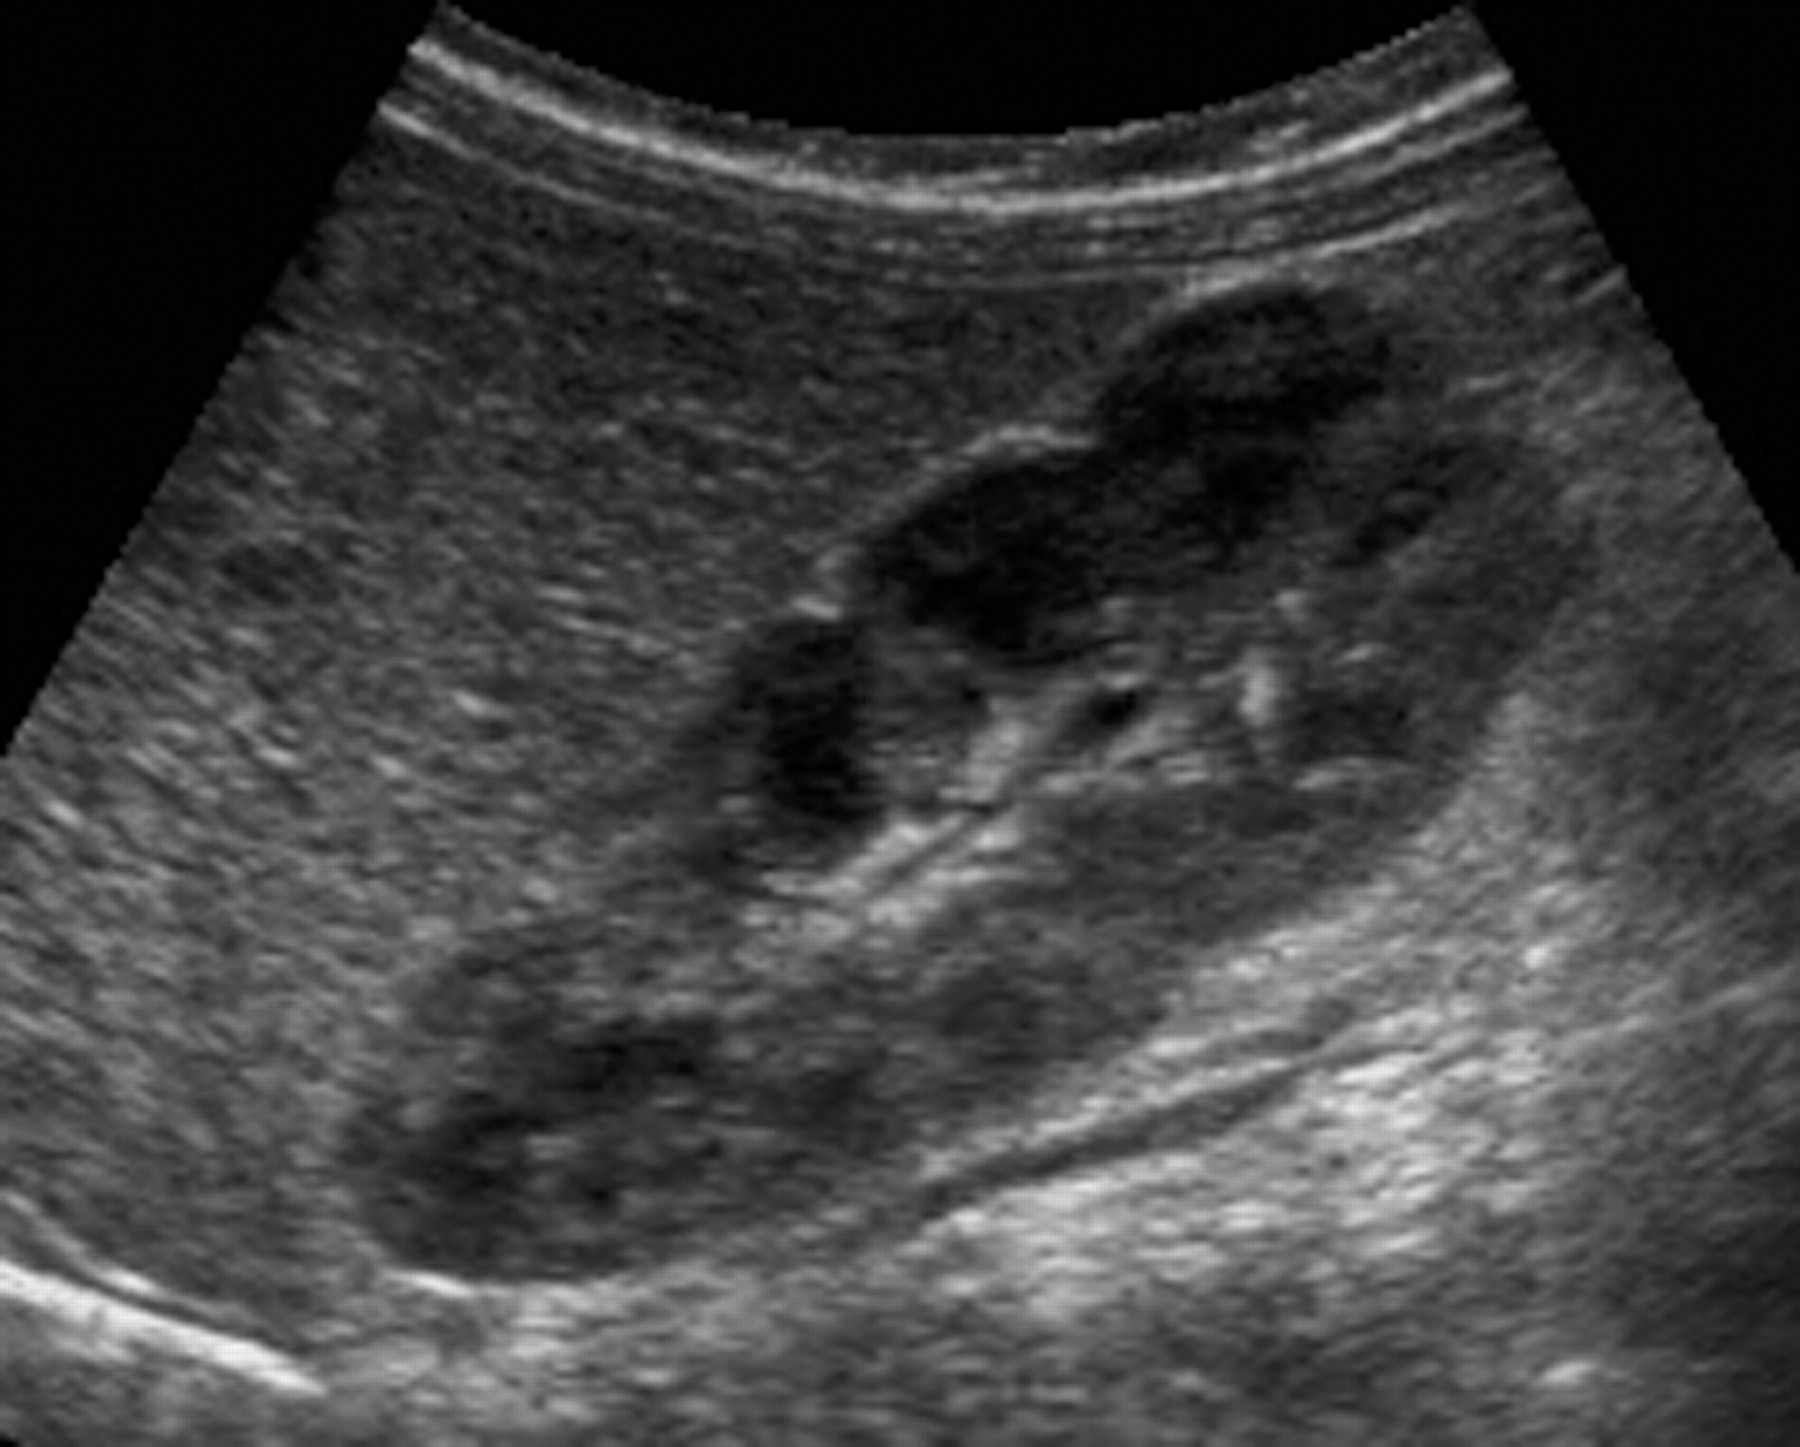

1-Hypertrophied column of Bertin

أعتقد بأن هذا من أهم المتغيرات التي قد يشتبه في كونها ورم. هي ببساطة تضخم لنسيج الكلية parenchyma إلى الداخل sinuses مرورا بين الأهرامات الكلوية medullary pyramids.

يميزه تناسق echogenicity بينه وبين باقي parenchyma بالإضافة لعدم وجود ارتفاع أو تغير ملحوظ في قراءات colour Doppler. غالبا لا يزيد عرضه عن ٣ سم.